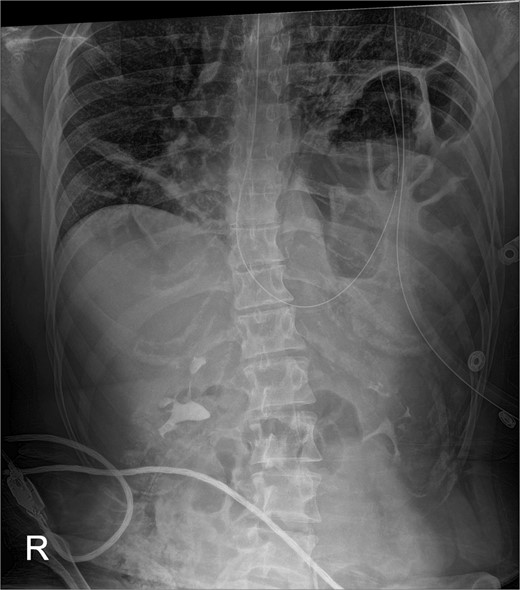

The early postoperative course was unremarkable. The patient reported feeling mild bloating, but was discharged on postoperative Day 1 after removal of a chest tube (Fig. 4). A few hours after discharge from the hospital, he developed dysphagia, progressive abdominal pain, distension, and dyspnea that prompted a return to the hospital. Physical examination revealed tachycardia (132 bpm), mild hypoxia requiring supplemental O2 at 2 L/min via nasal canula, and abdominal distension. Laboratory studies showed WBC of 12 600 cells/μL. A CT scan of the abdomen and pelvis revealed a large, acute organo-axial gastric volvulus without evidence of ischemia, and an intact left hemidiaphragm plication at a similar height to the right hemidiaphragm (Fig. 5). A nasogastric tube was placed with immediate drainage of 1 L of dark bilious fluid with immediate relief of the patient’s symptoms. However, a subsequent film revealed the nasogastric tube projecting toward the upper left chest with presence of colonic haustra (Fig. 6), consistent with acute hemidiaphragm rupture.

Confirmatory abdominal film for nasogastric tube placement demonstrating acute elevation in the left hemidiaphragm, 90-min after the CT, identifying the gastric volvulus.